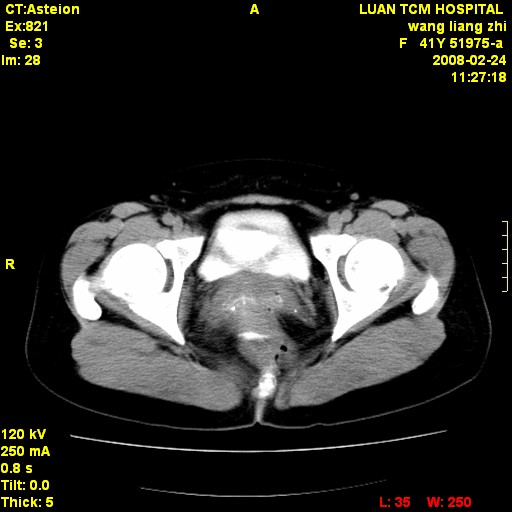

以下是引用dyqct在2009-8-23 16:17:00的发言:[br]考虑:1、造影剂进入腹腔、结肠旁沟、肝周;[br] 2、子宫明显增大(腺肌增生症?);[br] 3、膀胱显影是由于造影剂吸收后经肾分泌进入膀胱的;[br] 4、建议mri检查子宫。